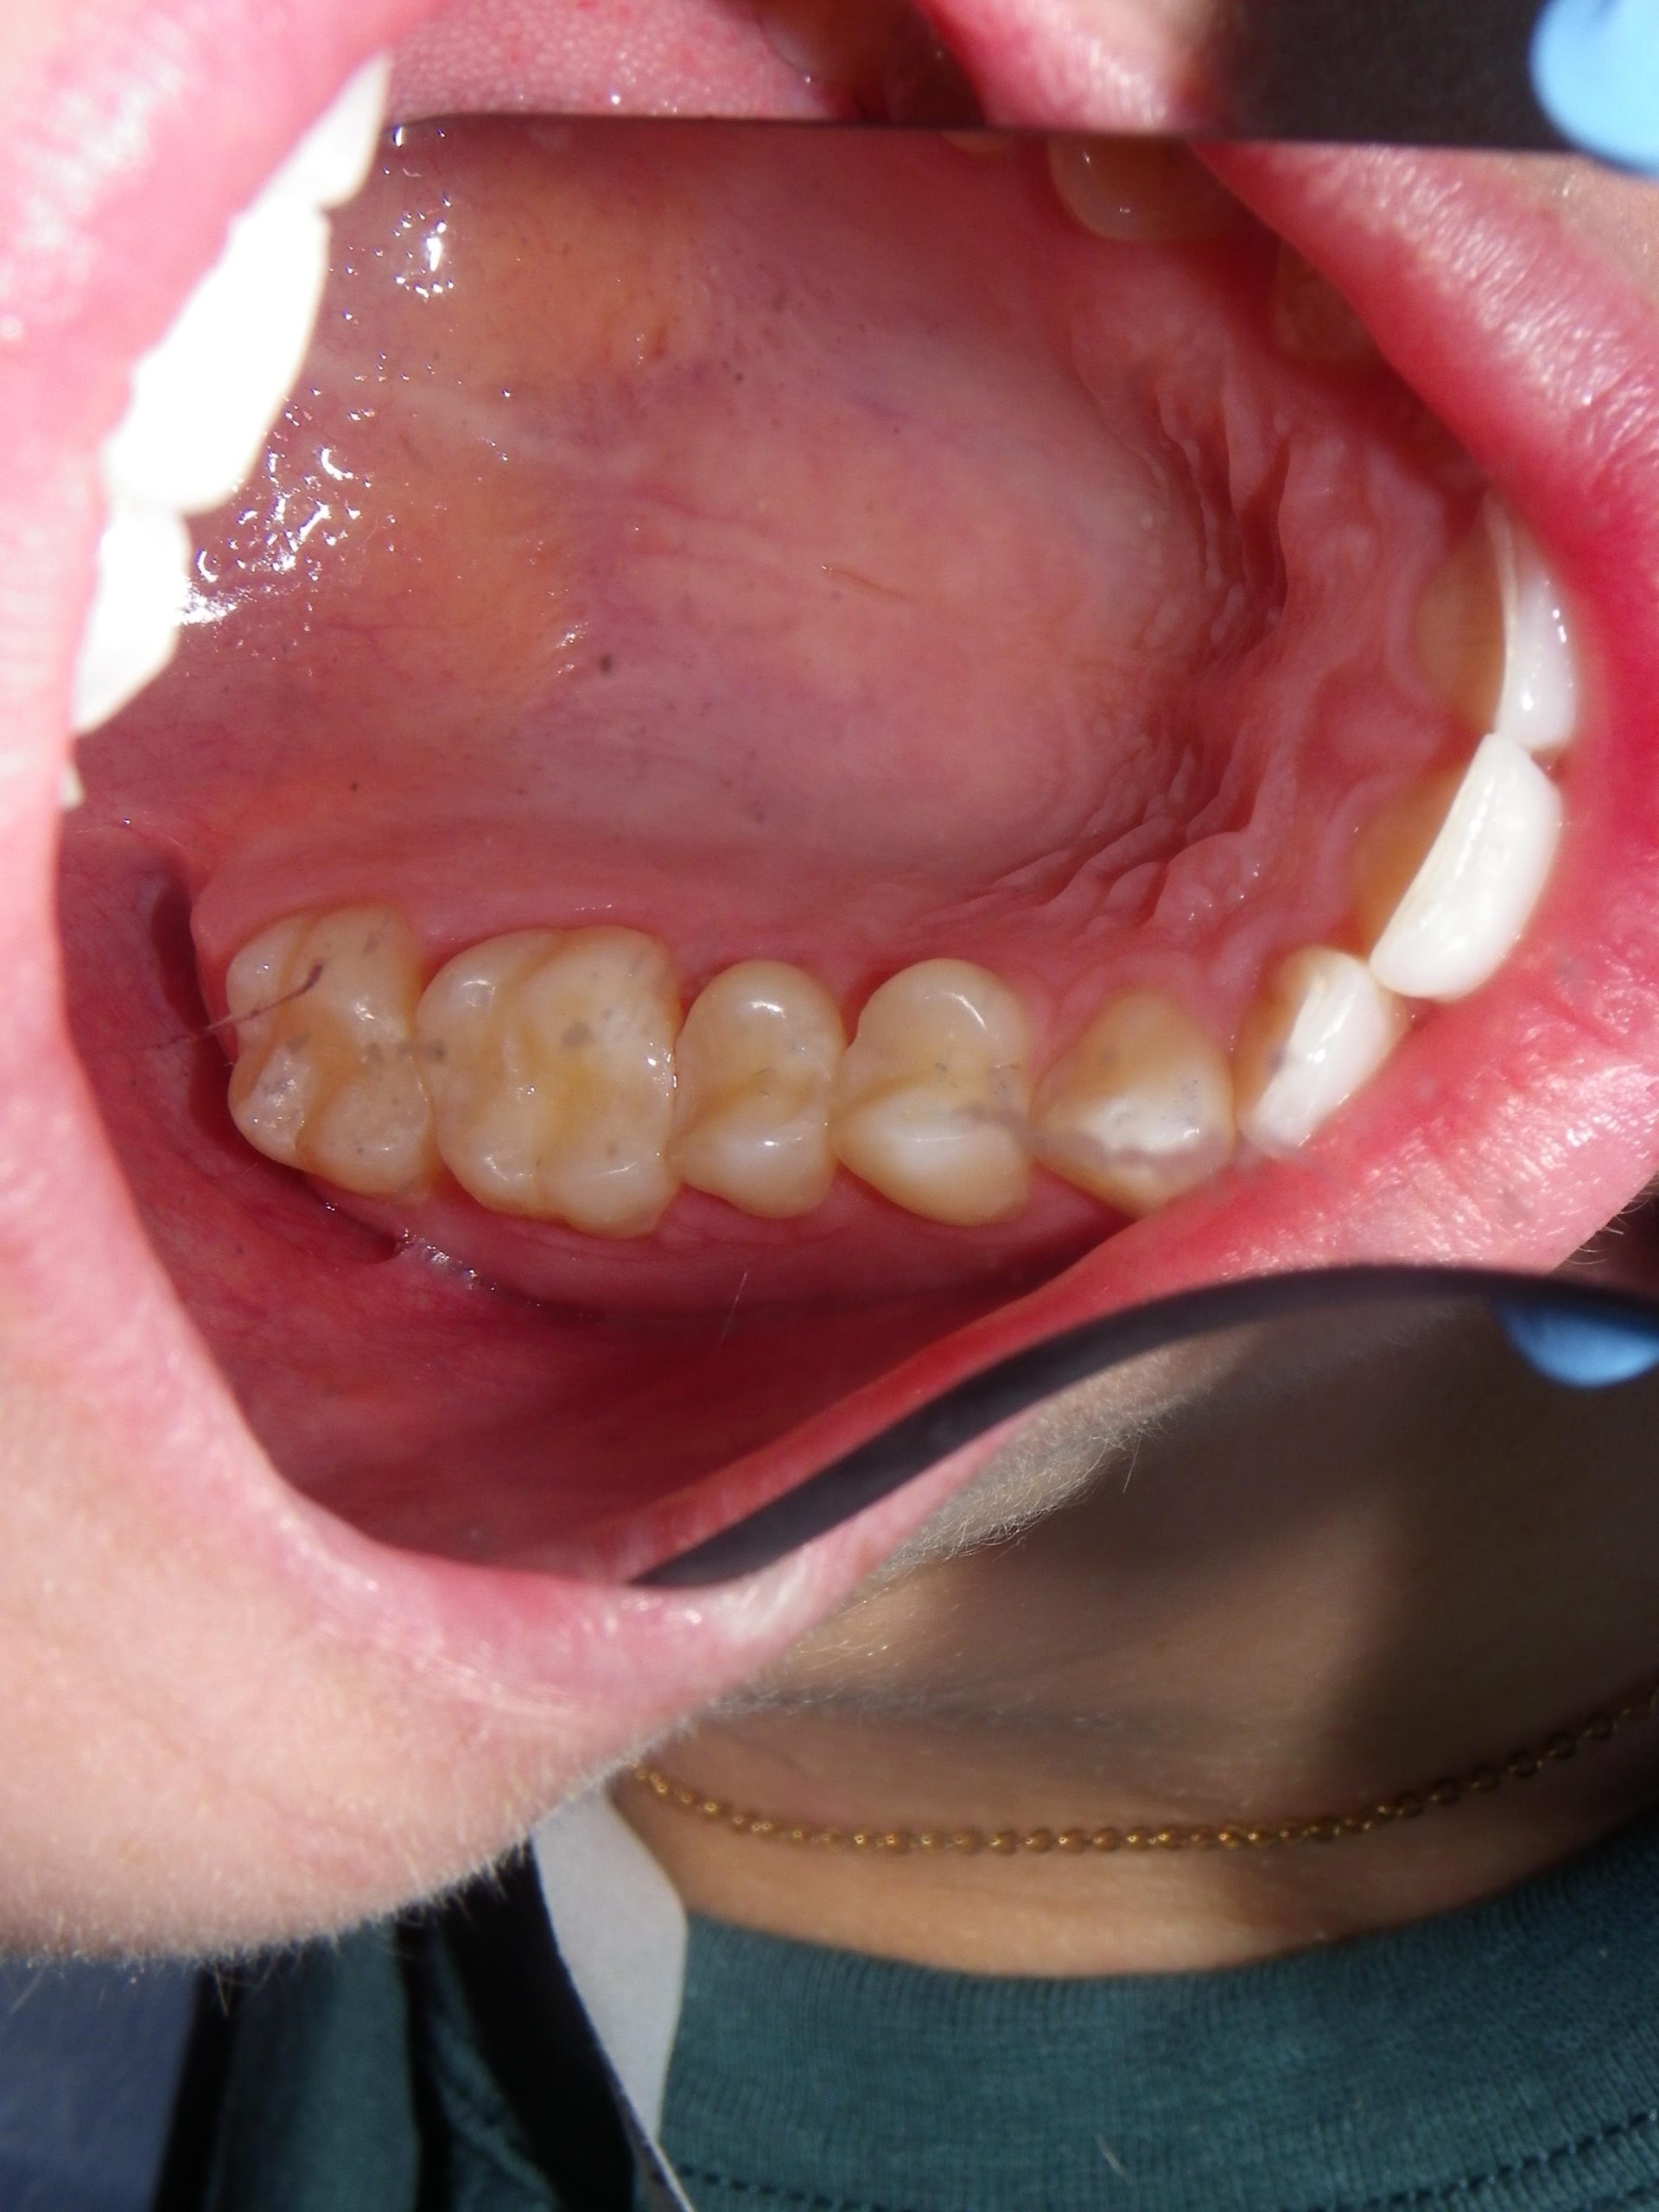

After educating the patient on the decay risks of this behaviour, oral hygiene instruction and a recommendation for a daily fluoride rinse, she can now take action to prevent any new cavities from developing for the rest of her life. There were many areas of decay between other teeth that we elected not to fill due to their small size, and hopefully they remain arrested / remineralized! (Aluminum oxide Air abrasion via PrepStart, 32% Phosphoric acid etch with Benzalkonium Chloride and AllBond Universal adhesive from Curion, Esthet-X Flowable A2 liner from Dentsply, Simplishade Medium resin core from Kerr).